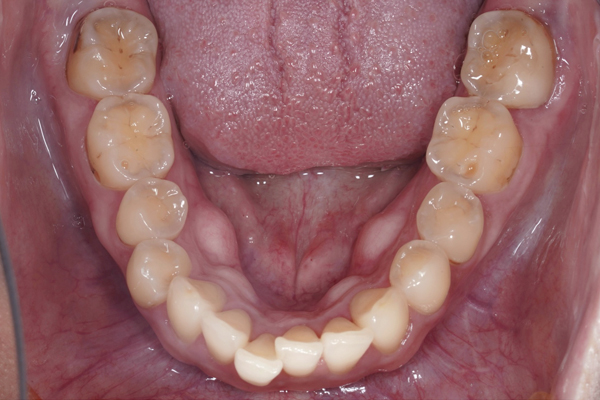

上の歯の比較(咬合面)

下の歯の比較(咬合面)